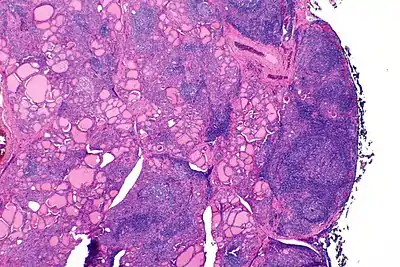

Gross pathology of a thyroid with autoimmune thyroiditis may show an symmetrically enlarged thyroid.[22] It is often paler in color, in comparison to normal thyroid tissue which is reddish-brown.[22] Microscopic examination will show infiltration of lymphocytes and plasma cells. The lymphocytes are predominately T-lymphocytes with a representation of both CD4 positive and CD8 positive cells.[22] The plasma cells are polyclonal, with present germinal centers resembling the structure of a lymph node.[22] Fibrous tissue may be found throughout the affected thyroid as well.[22] Generally, pathological findings of the thyroid are related to the amount of existing thyroid function - the more infiltration and fibrosis, the less likely a patient will have normal thyroid function.[22] In late stages of the disease, the thyroid may be atrophic.[12]

Histologically, the hypersensitivity is seen as diffuse parenchymal infiltration by lymphocytes, particularly plasma B-cells, which can often be seen as secondary lymphoid follicles (germinal centers, not to be confused with the normally present colloid-filled follicles that constitute the thyroid). Atrophy of the colloid bodies is lined by Hürthle cells, cells with intensely eosinophilic, granular cytoplasm, a metaplasia from the normal cuboidal cells that constitute the lining of the thyroid follicles. Severe thyroid atrophy presents often with denser fibrotic bands of collagen that remains within the confines of the thyroid capsule.[52]

It is also characterized by invasion of the thyroid tissue by leukocytes, mainly T-lymphocytes. A rare but serious complication is thyroid lymphoma, generally the B-cell type, non-Hodgkin lymphoma.[53]